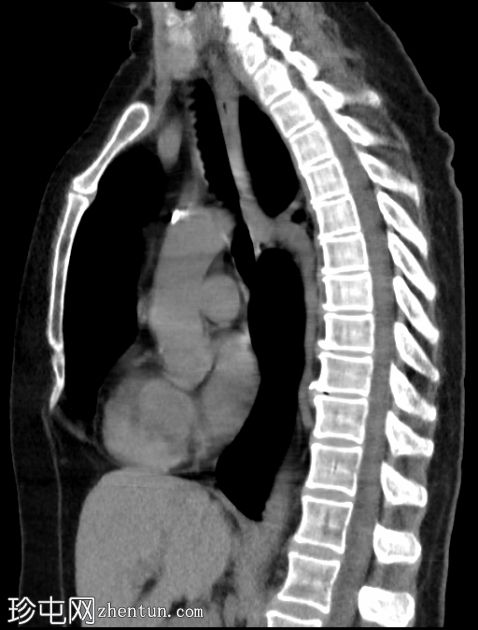

双侧肺(尤其是上叶)广泛融合性小叶中心型肺气肿。

左上叶肺瘢痕形成,可能是先前感染的后遗症。

双侧乳房植入。

早期小叶中心性肺气肿通常表现为小(<1 mm 至 3 cm)、圆形、均匀分布、边界不清的透亮区,可能出现在小叶中心动脉周围的次级肺小叶中央部分,而在严重的情况下,低衰减区会融合且不可分离,并且失去小叶中心分布。